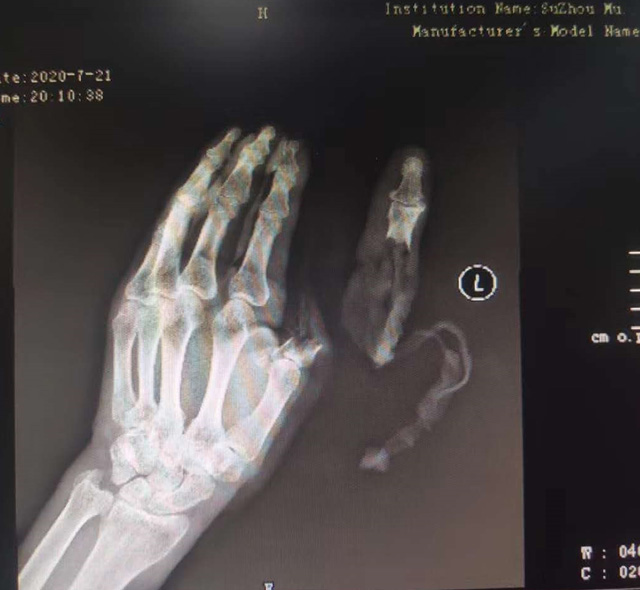

現(xiàn)代快報記者了解到,7月21日下午,這名76歲的老人在家擦拭面粉機時,忘記關(guān)閉電源,結(jié)果抹布被纏進機器,順帶著將老人的手也帶進機器中。老人奮力掙脫,可為時已晚,待將手取出時,已經(jīng)血肉模糊,大拇指在脫落后還被絞入機器軋了一圈……

△老人送醫(yī)時的手部狀態(tài) 蘇州市立醫(yī)院供圖

拇指可以影響一只手40%的功能,為此醫(yī)院立即制定了手術(shù)方案,決定為老人進行斷指再植術(shù),盡力為其保住拇指。由于該患者年紀大、血管彈性差,動脈血管分層也很嚴重,面對重重困難,醫(yī)生在顯微鏡的輔助下,小心翼翼地將血管、神經(jīng)重新吻合,并修復肌腱、皮膚。經(jīng)過5個多小時努力,最終再植成功。

經(jīng)過和患者反復溝通,醫(yī)生決定為老人選擇腹部帶蒂皮瓣手術(shù)。即先將發(fā)黑壞死的皮膚清除,再將腹部皮膚覆蓋在手部皮膚缺損處。8月24日,醫(yī)生在老人右下腹設(shè)計了一個皮瓣,將老伯的左手拇指用皮瓣覆蓋。經(jīng)過3周的精心護理,斷指成功“復活”。9月14日,醫(yī)生將皮瓣蒂部斷開,此時,皮瓣和拇指重新建立了可靠的血運,不僅拇指保住了,長度也和以前的一樣。